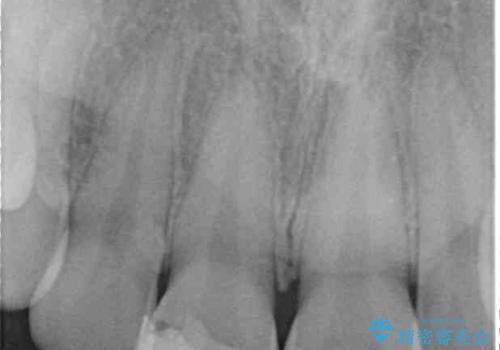

転倒などの強い力がかかった歯は、歯の内部の歯髄組織が壊死してしまったり、外部吸収と知って、歯根の一部が吸収してしまったりと、思わぬ問題を抱えていることがあります。

治療期間においてはこのようなトラブルは発生していませんでしたが、今後も定期的にレントゲン写真撮影などで経過を見ていく必要があります。